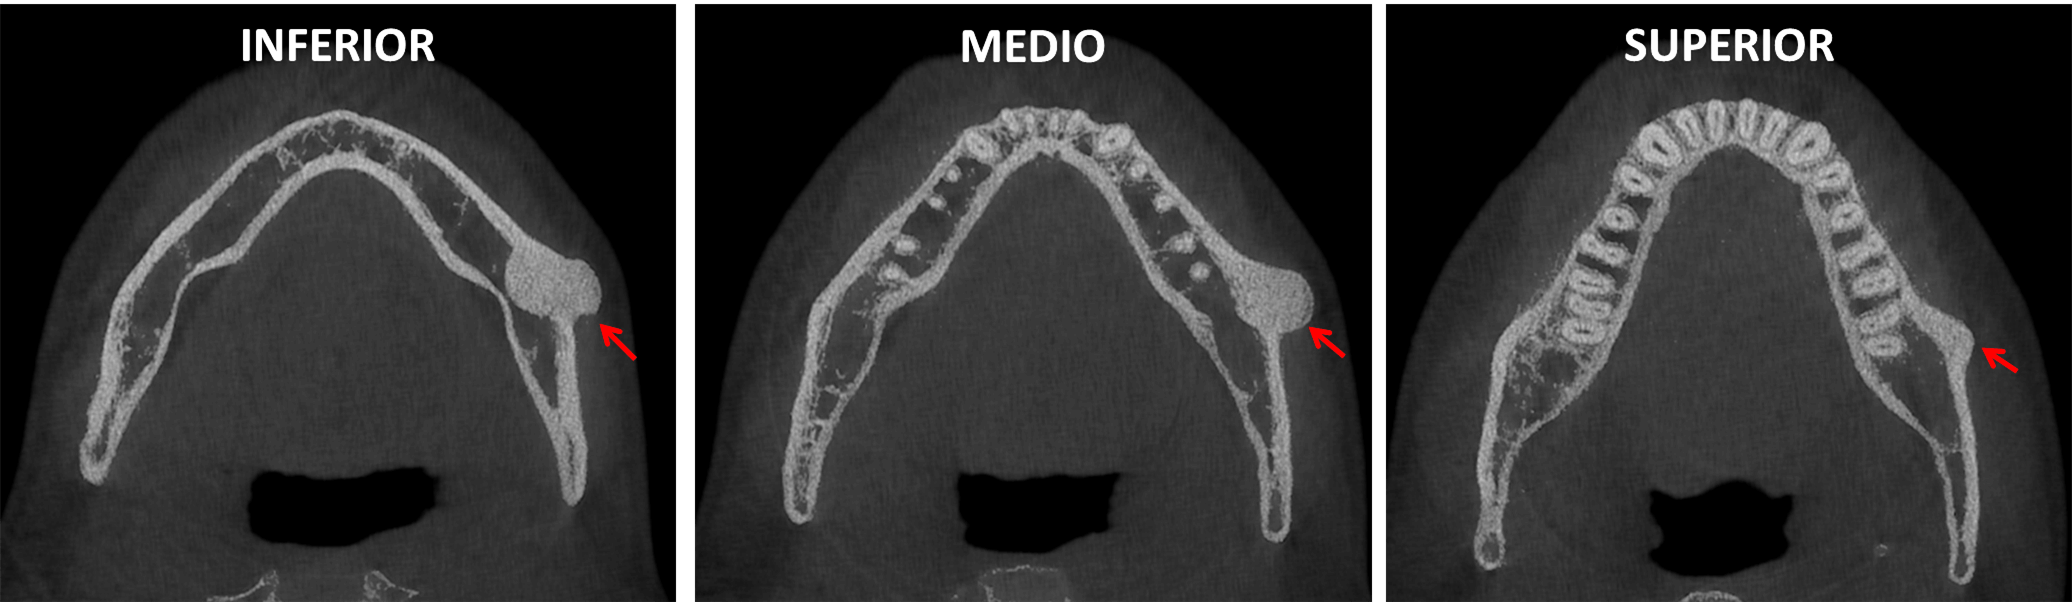

Osteoma Periférico en Mandíbula Dento Metric Radiología Dental Dental Osteoma Osteoid osteoma of the maxilla may present as pain related to dental implants and. Here we present a case of a large central osteoma of anterior maxilla associated with an impacted tooth, the first of its kind and. Osteomas are benign neoplasm often associated with facial asymmetry, pain and surface ulceration. Peripheral osteomas have been described to occur in the. Dental Osteoma.

Osteoma Periférico en Mandíbula Dento Metric Radiología Dental Dental Osteoma Here we present a case of a large central osteoma of anterior maxilla associated with an impacted tooth, the first of its kind and. Peripheral osteomas have been described to occur in the frontal, ethmoid, and maxillary sinuses, but are not common in. Osteomas are benign neoplasm often associated with facial asymmetry, pain and surface ulceration. Osteoblastoma and osteoid osteoma. Dental Osteoma.

Osteoma Periférico en Mandíbula Dento Metric Radiología Dental Dental Osteoma We reviewed current literature surrounding the ongoing. Osteomas are benign neoplasm often associated with facial asymmetry, pain and surface ulceration. Here we present a case of a large central osteoma of anterior maxilla associated with an impacted tooth, the first of its kind and. Peripheral osteomas have been described to occur in the frontal, ethmoid, and maxillary sinuses, but are. Dental Osteoma.

Osteoma Periférico en Mandíbula Dento Metric Radiología Dental Dental Osteoma Peripheral osteomas have been described to occur in the frontal, ethmoid, and maxillary sinuses, but are not common in. Osteoblastoma and osteoid osteoma are rare benign neoplasms of the jaws. Osteomas are benign neoplasm often associated with facial asymmetry, pain and surface ulceration. Here we present a case of a large central osteoma of anterior maxilla associated with an impacted. Dental Osteoma.